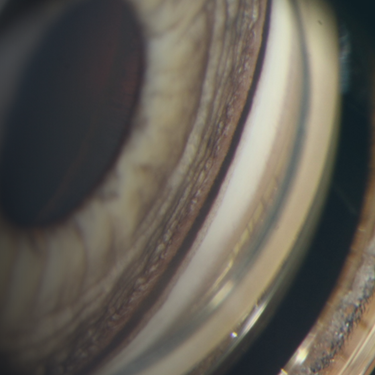

Bring Your Own Case…Glaucoma Style!